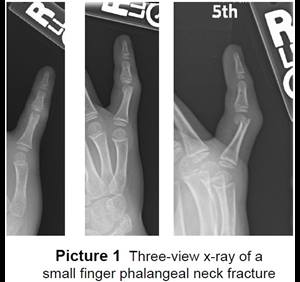

- The surgeon will do a closed reduction and/or pinning. Pins are pushed into the skin to hold the pieces of bone together until the they heal (Picture 2). The ends of the pins on the outside of the skin are bent (Picture 3).

- At the end of surgery, your child’s hand will be in a cast or splint and the pins are covered up.